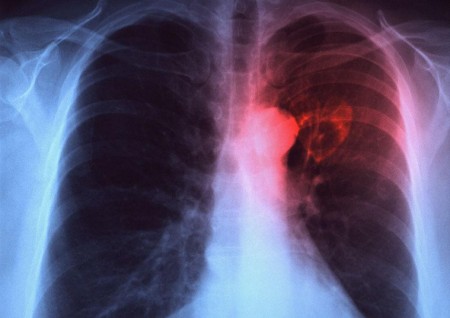

TUMORE-POLMONE

TUMORE-POLMONESono cellule immunitarie ma invece di assolvere alla loro tradizionale missione di proteggerci, aiutano il tumore ai polmoni a svilupparsi. È uno studio tutto italiano portato avanti da un gruppo di scienziati e in cui l’Università di Messina è protagonista con il professor Guido Ferlazzo.